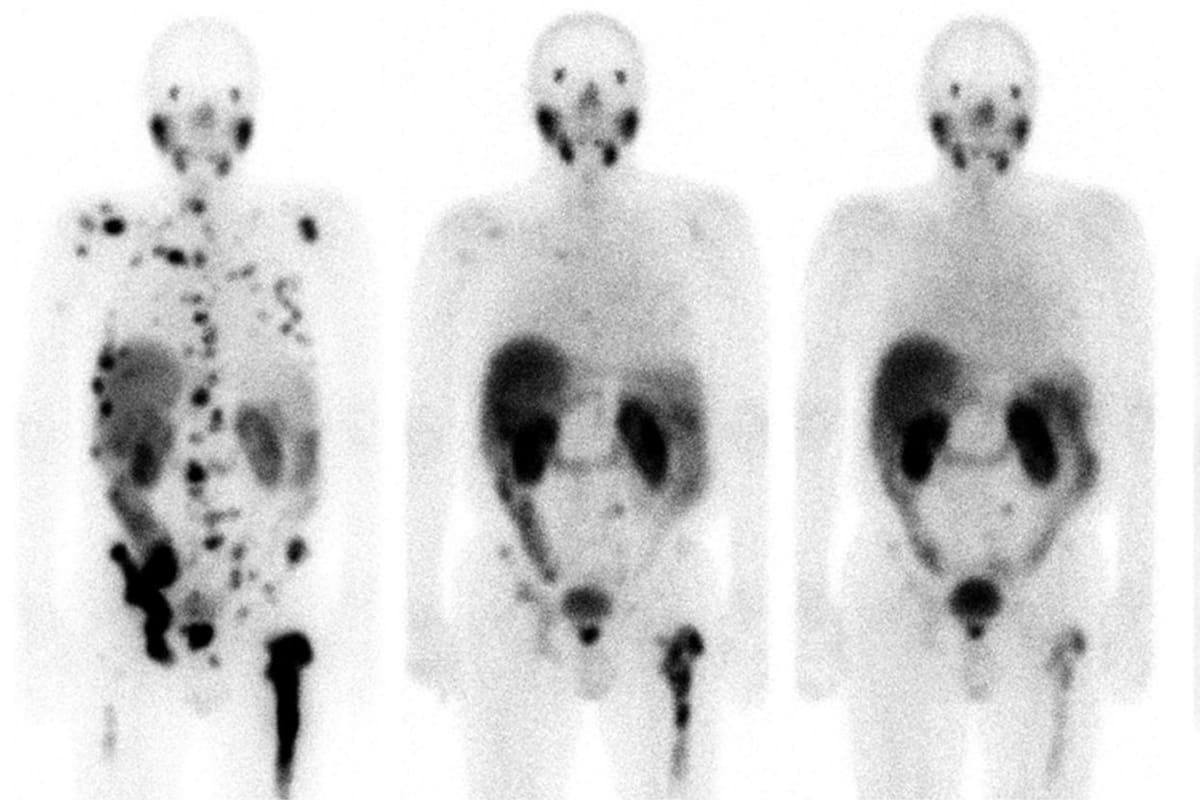

El médico recuerda el caso de un hombre alemán de 62 años, con cáncer de próstata y una diseminación masiva con metástasis en los huesos. Tras un tratamiento experimental con teragnosis en la Clínica Central de Bad Berka (Alemania), ocho meses después parecía limpio. Volvió a trabajar y a hacer deporte. Y tres años y medio después seguía libre de cáncer, según explicó Carreras en febrero en una sesión científica en la Real Academia Nacional de Medicina, en Madrid.

Para hacer el diagnóstico, esa molécula afín al PSMA se une a un elemento químico radiactivo, el galio-68, que brilla en una exploración con tomografía por emisión de positrones (PET). Para el tratamiento, la misma molécula se une a otro elemento químico, el lutecio-177, que emite una radiación local que mata a las células cancerosas. Es como disparar primero una flecha con una bombilla y después otra flecha con una pequeña carga explosiva.

En el ensayo de Morris participaron 831 pacientes con cáncer de próstata resistente a la castración y metástasis, un tipo de tumor habitualmente letal. Los enfermos que recibieron el tratamiento con teragnosis vivieron 15,3 meses, frente a los 11,3 meses de los hombres a los que se administró una terapia estándar. Cuatro meses de diferencia -un 35% más- pueden parecer poca cosa, pero se trataba de pacientes prácticamente desahuciados, en los que ya habían fallado la quimioterapia y los tratamientos hormonales.